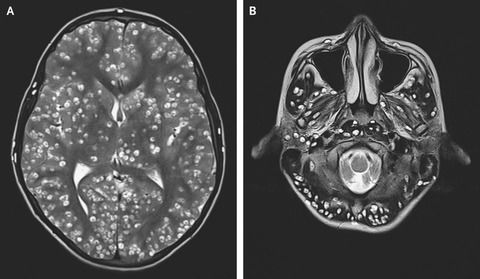

男性の脳や肺などから700超の寄生虫 火鍋の豚肉が原因か 中国 19年11月23日 エキサイトニュース

Cnn Co Jp 発作を起こした男性 脳内にサナダムシが寄生 鍋料理の肉が原因か 中国

数百匹のサナダムシが 頭痛を訴えた中国人男性の脳に ニューズウィーク日本版 オフィシャルサイト